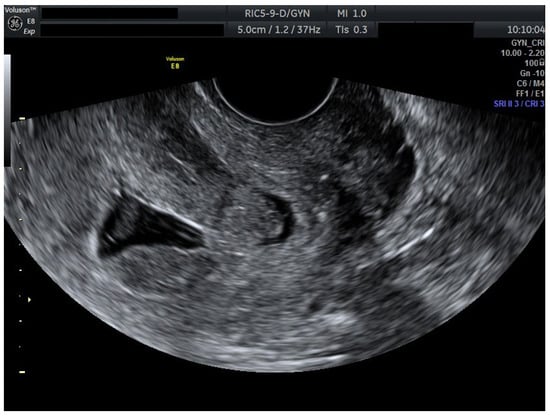

We present a personal case from our tertiary center in western Romania as an example of applicable findings from this review. A 32-year-old woman presented to the Municipal Clinical Emergency Hospital of Timișoara with first-trimester vaginal bleeding. Transvaginal ultrasound revealed a viable intrauterine gestation with a seven-week-old embryo with positive cardiac activity, as well as a simultaneous viable CP, confirming the diagnosis of HCP (Figure 1).

Figure 1.

Ultrasound evaluation at diagnosis with viable heterotopic embryos (Day 0). Combined ultrasound of both gestational sacs. Transvaginal ultrasound evaluation: sagittal view through the uterus and cervical canal. FHR present in both embryos. Patient information is anonymized.